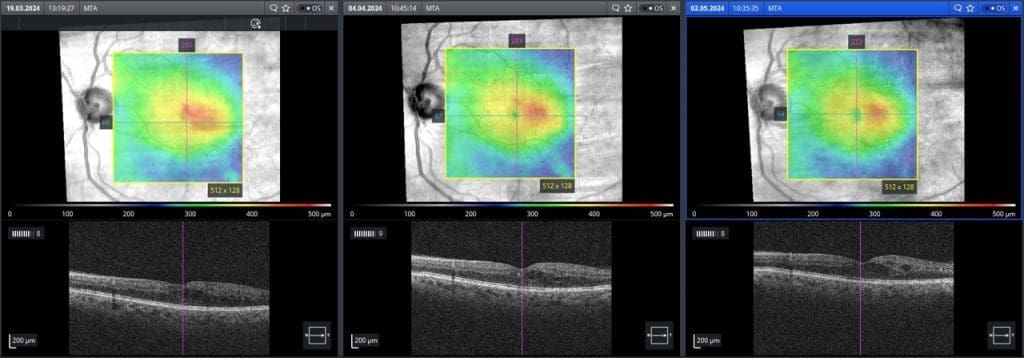

Die Intervalle der Kontrolluntersuchungen und die Therapie erfolgen in Abhängigkeit der Ausprägung pathologischer Veränderungen: Liegen keine oder milde Veränderungen vor, erfolgt eine jährliche Kontrolle. Bei sichtbaren Veränderungen – vor allem bei ödematösen Veränderungen im Bereich der Fovea – sind eine zeitnahe ärztliche Vorstellung (so auch beim Patienten aus Abbildung 1), bzw. Kontrollen in Intervallen zwischen 2 Wochen (bei schweren Veränderungen) und sechs Monaten (bei moderaten Veränderungen) angezeigt.3,4

Die Therapie des Patienten aus Abbildung 1 erfolgte mittels in den Glaskörper injizierten VEGF-Inhibitoren (intravitreale Injektionen, abgekürzt häufig IVOM). Die OCT-Befunde des Therapieverlaufs sind in Abbildung 2 dargestellt.